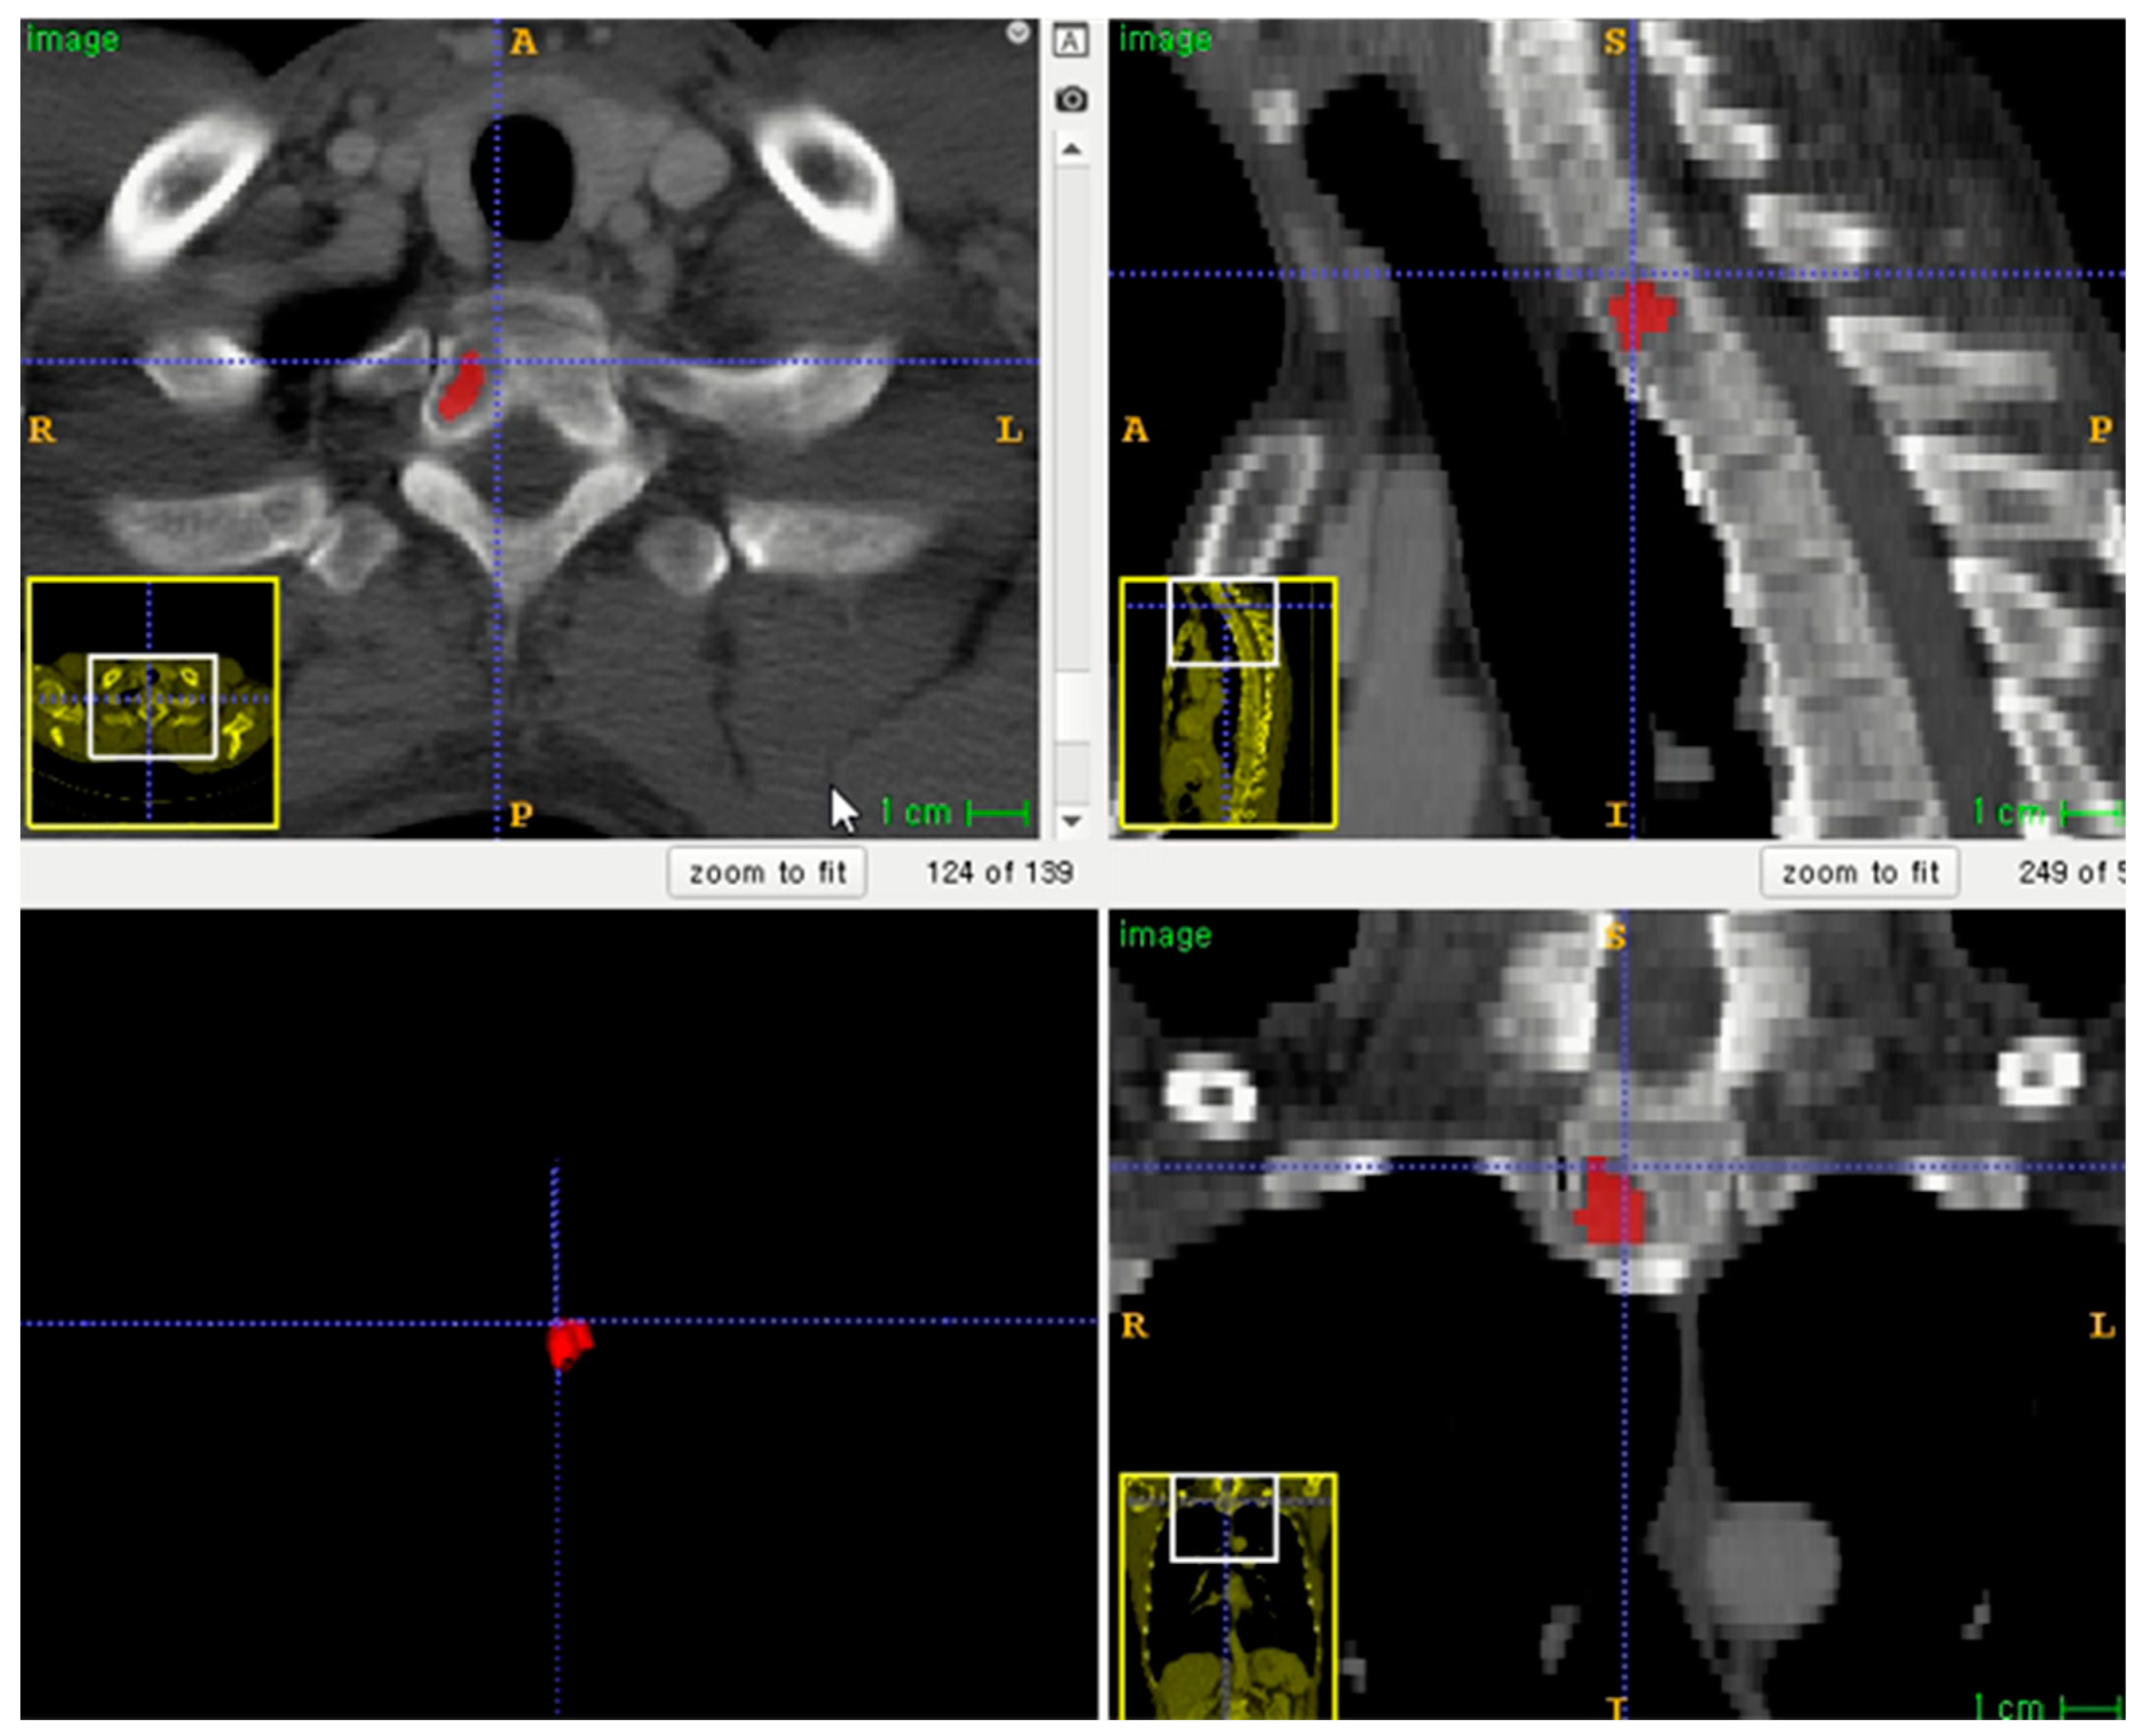

The entire volume of interest (VOI) was manually segmented based on contrast-enhanced CT images. Segmentation was performed using an open-source program (ITK-SNAP software, version 3.8.0, http://www.itksnap.org, accessed on 1 December 2020) (Figure 2) [16]. To correct the variability of voxel size, segmented VOIs were resampled to isometric voxels of 1 mm × 1 mm × 1 mm [17]. The radiomics features of VOI segmentation were extracted using the PyRadiomics package (https://github.com/Radiomics/pyradiomics/, accessed on 10 June 2021) [18]. VOI segmentation was performed by one trained technologist (K.-E.L., with 2 years of experience in medical imaging segmentation). A radiologist (S.-Y.L.) supervised the segmentation.

Figure 2.

Example of lesion segmentation on axial skeleton.